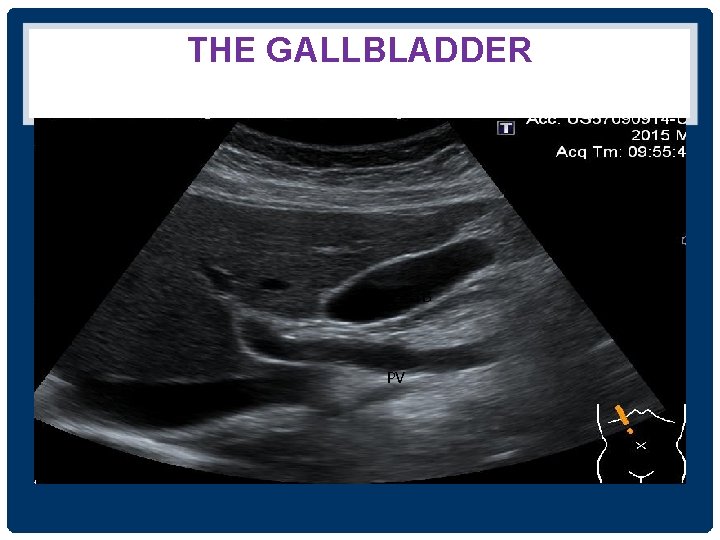

THE GALLBLADDER • อยใต interlobar fissure • ใชเปน landmark for identifying the junction between the left and right lobes of the liver • งดนำงดอาหาร ประมาณ 4 -6 ชวโมง adequate gallbladder distention + reduce upper abdominal bowel gas

THE GALLBLADDER GB PV